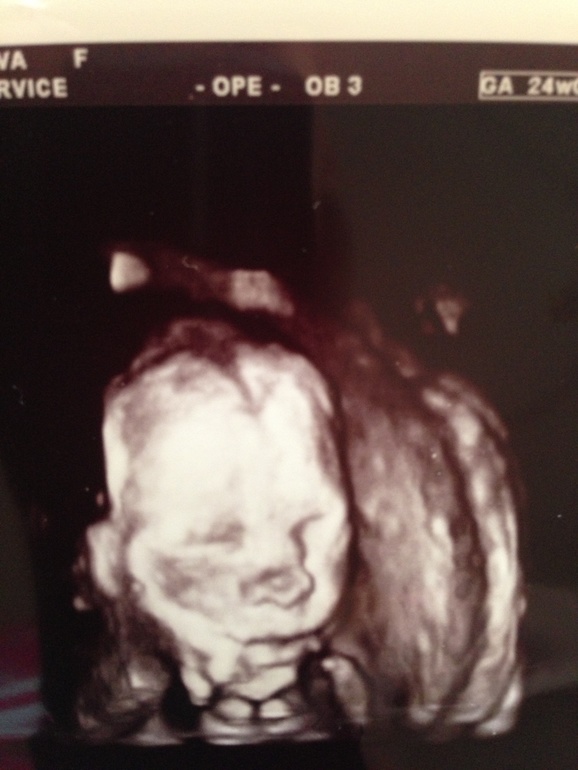

Полных 23 недели.

После всех этих больниц и лекарств я собираюсь завтра записаться на узи, последний раз в 19 н делала. Было все ок!